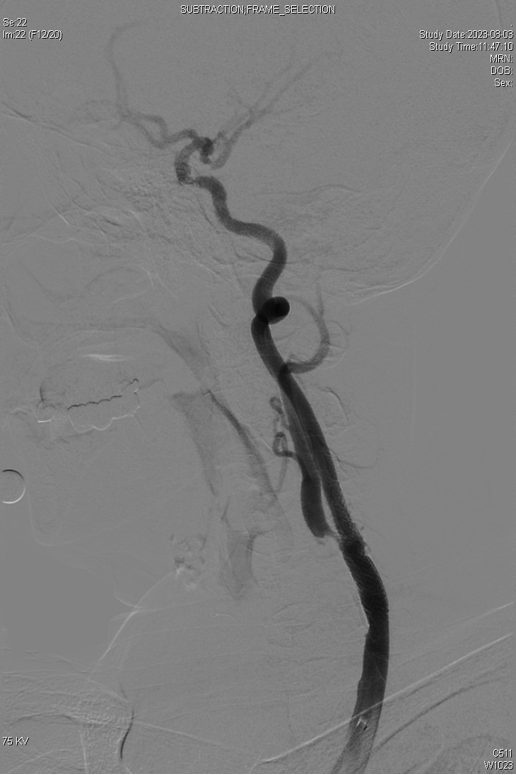

CASE 2:69岁男性,左侧颈动脉支架术后再狭窄,IVL治疗后管腔获得良好,支架置入后残余狭窄低。

左侧颈动脉支架

术后再狭窄

IVL后管腔

获得良好

支架后

残余狭窄低